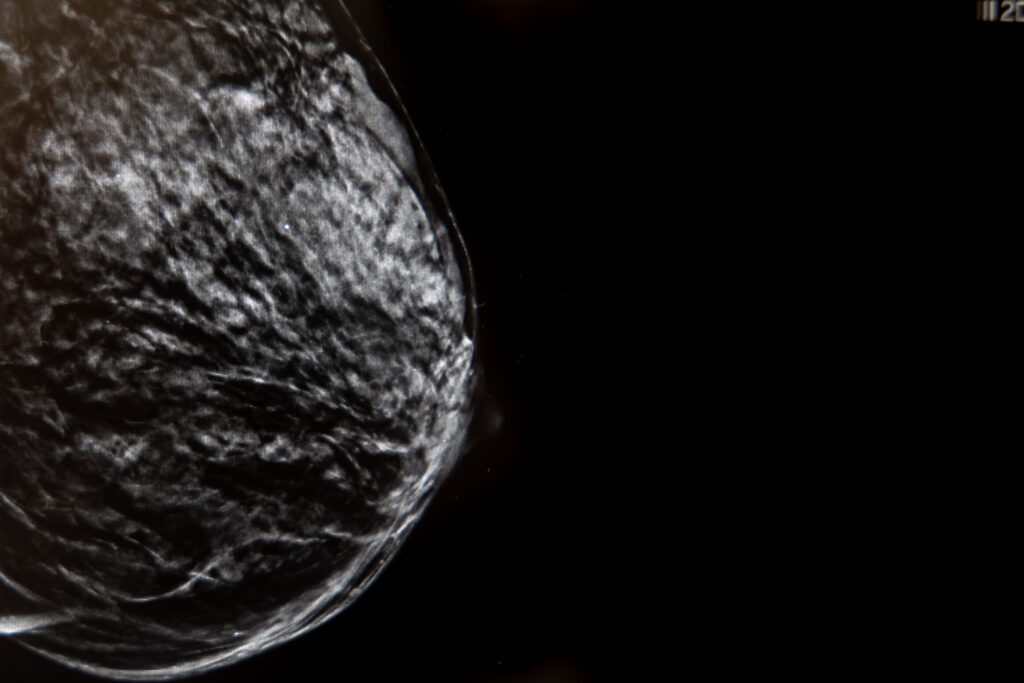

La mamografía con tomosíntesis, también conocida como mamografía 3D, es una técnica avanzada de imagen mamaria que utiliza rayos X de baja dosis para crear una imagen tridimensional de la mama. A diferencia de la mamografía tradicional, que proporciona una imagen bidimensional, la tomosíntesis captura múltiples imágenes desde diferentes ángulos, permitiendo una visualización más detallada del tejido mamario.

- Detección de cáncer de mama: permite identificar tumores pequeños que podrían pasar desapercibidos en una mamografía convencional, especialmente en mamas con alta densidad de tejido.

- Mayor precisión en mamas densas: reduce la superposición de los tejidos, mejorando la visualización de las estructuras mamarias en mujeres con mamas densas.